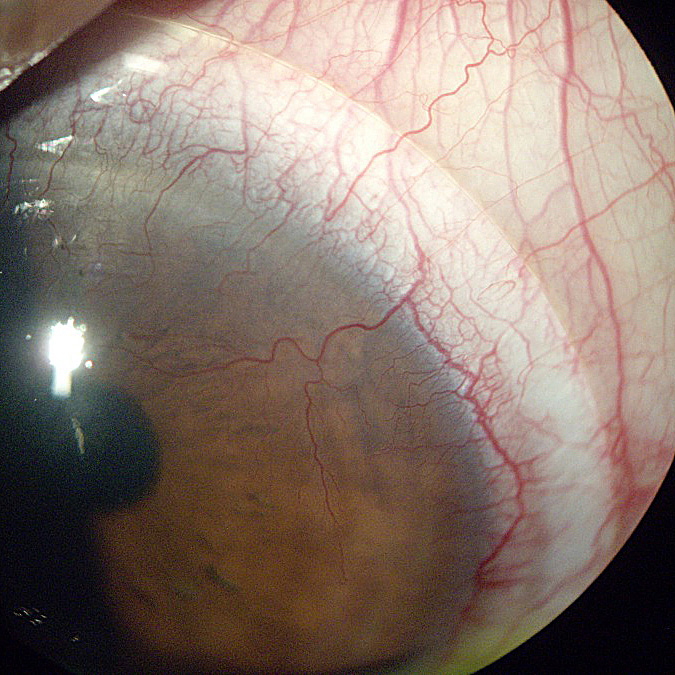

Corneal Neovascularization can be defined as the excessive growth of blood vessels that occurs at the level of the cornea. The main cause of the problem is represented by the oxygen deprivation. In healthy individuals, the cornea is transparent and it lacks vascularization. Both ocular insults and ocular hypoxia are responsible for the appearance of corneal vascularization.

- Limbal hyperemia (Redness around the cornea) – earliest sign of corneal neovascularization.

- Superficial vessels identified at the level of the cornea (single or multiple).

- In the situation that the deep stromal vessels are responsible for the corneal neovascularization, these are identified at the level of the cornea (sometimes accompanied by nerve fibres).

- Active engorged vessels and lipid exudate.

- Corneal edema and leakage.

The invasion of the cornea by the deep stromal vessels presents the biggest risks, with the optical transparency being lost due to a series of changes. Among the most important changes, there are the hemorrhage and scarring that can occur at the level of the cornea. The deposits of lipids can also affect the optical transparency, complicating the already existent corneal neovascularization.